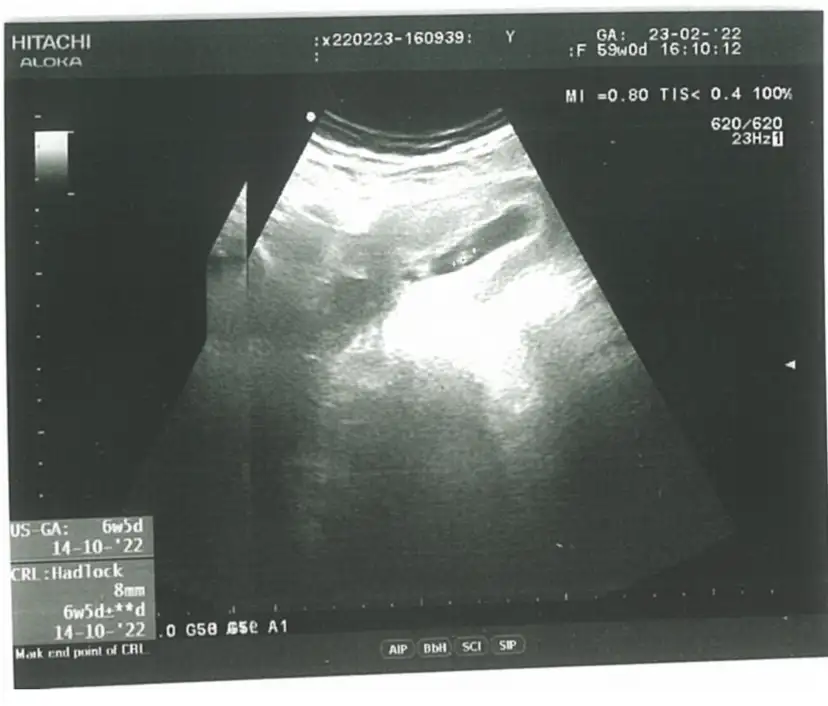

Maşallah canımEki Görüntüle 3014538

Benim ultrason görüntüm de bu